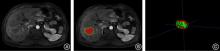

Huiliang CAI,Qianying ZHANG,Ying HUANG,Weisheng PENG,Chengli WANG,Cuiting YANG,Na DENG,Sizhu ZHANG,Nina XU,Xiaobing HAN. Assessments of ki⁃67 expression in hepatocellular carcinoma using enhanced MRI intratumoral and peritumoral radiomics and clinical imaging features[J]. The Journal of Practical Medicine, 2025, 41(15): 2311-2319.